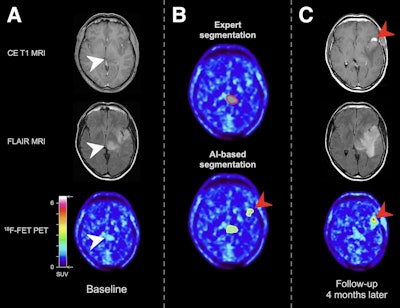

Baseline scan (A), segmentation results (B), and follow-up scan (C) from patient with molecular glioblastoma. Baseline MRI showed FLAIR hyperintensities in left thalamus and frontoparietal region (white arrowheads). In contrast to expert segmentation, in which only left thalamic region showed slightly increased uptake (red contour), AI algorithm identified additional frontoparietal lesion on baseline PET that subsequently progressed to contrast-enhancing and metabolically active lesion (red arrowheads). Image courtesy of the Journal of Nuclear Medicine.

An analysis of the PET scan by an experienced nuclear medicine physician showed an increase in F-18 FET radiotracer uptake that revealed a potential tumor in the patient’s left thalamic region, the authors noted.

Subsequently, the researchers tested their JuST_BrainPET tool on the baseline F-18 FET-PET image.

“Surprisingly, a second lesion in the frontoparietal region, not segmented by the expert, was identified by the AI algorithm,” the group wrote.

Moreover, on follow-up imaging four months later, the patient’s left thalamic lesion showed no progression, while the additional frontoparietal lesion identified by the AI model had progressed to become a small contrast-enhancing and metabolically active tumor, the group wrote.